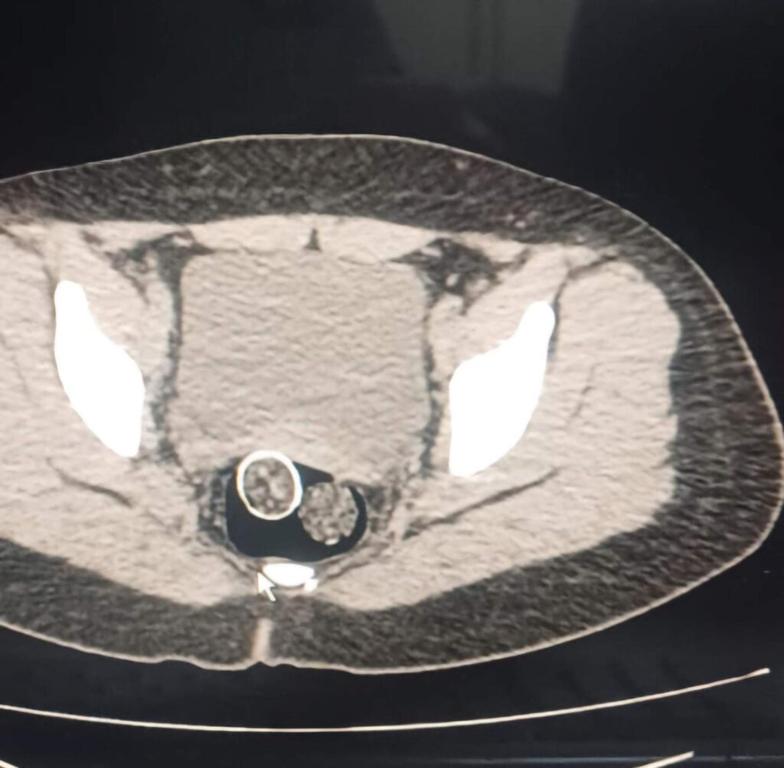

25 Kasım 2024 günü Narkotik Suçlarla Mücadele Şube Müdürlüğümüzce uyuşturucu veya

uyarıcı madde ticareti yapan şahıs veya organizasyonlara yönelik yapılan operasyonda (5) şüpheli

şahıs yakalanmış, iki şahsın yaptırılan iç beden muayenesinde ve kullandıkları iki araçta yapılan

aramada;